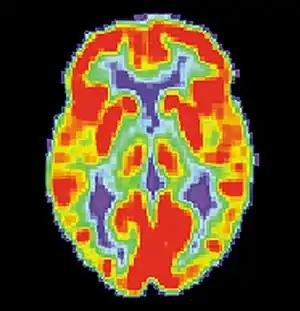

![]() PET scan of a normal brain | |

Brain positron emission tomography is a form of positron emission tomography (PET) that is used to measure brain metabolism and the distribution of exogenous radiolabeled chemical agents throughout the brain. PET measures emissions from radioactively labeled metabolically active chemicals that have been injected into the bloodstream. The emission data from brain PET are computer-processed to produce multi-dimensional images of the distribution of the chemicals throughout the brain.[1]: 57